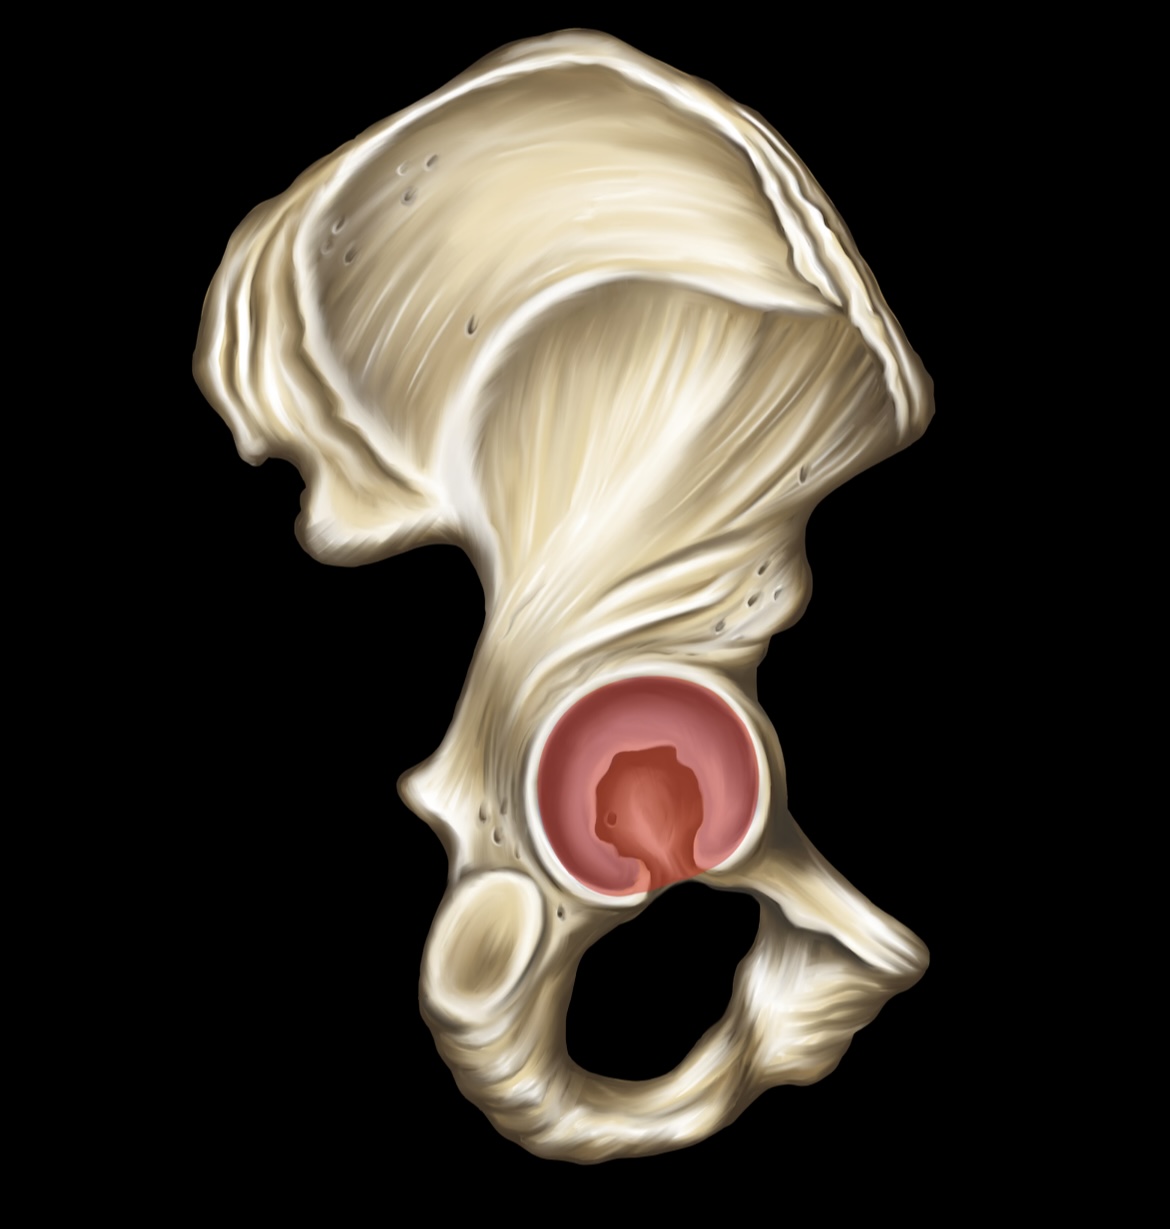

Illium

Ischium

Pubis

Ischial Spine of Ischium

Iliac Tuberosity of Illium

Anterior Superior Iliac Spine

Anterior Inferior Iliac Spine

Posterior Superior Iliac Spine

Posterior Inferior Iliac Spine

Iliac Crest

Acetabulum